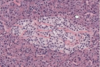

In the histology section of the colon below, what do the numbers 1, 2 and 3 relate to?

1 - lamina propria

2 - muscularis mucosa

3 - gland